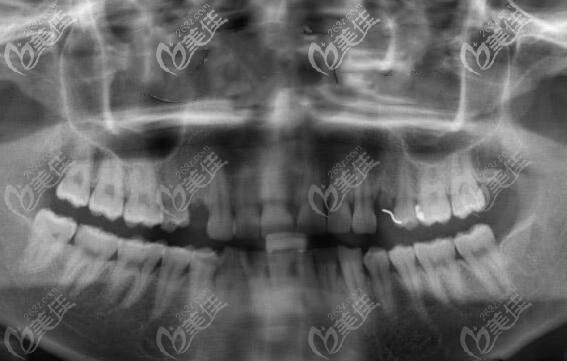

制定方案后,就幫顧客免費(fèi)拍了口腔CT全景片,從CT片中可以看出來有單顆缺失,但是牙槽骨條件良好,無炎癥,做種植也比較簡單,性價(jià)比比較高的韓國登騰種植體就可以做。

天津雅爾美口腔的醫(yī)生就利用數(shù)字化電腦進(jìn)行了簡單的設(shè)計(jì),避開血管神經(jīng),確種植體的位置,以及種牙后的牢固性。確方案后就開始手術(shù)。